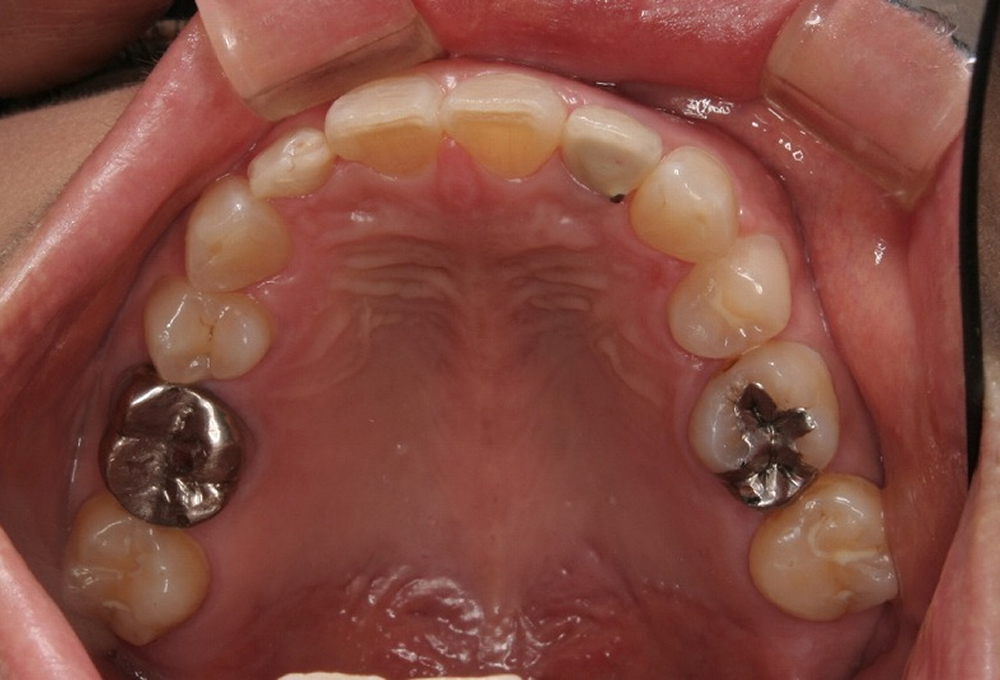

②術前上顎